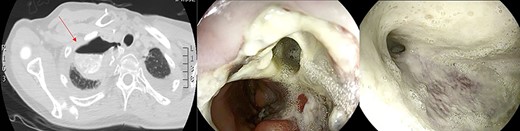

Large anastomotic leakage after minimally invasive esophagectomy opening to a cavity in the pleural space of 8 cm in size.

On the third postoperative day (POD), inflammatory indexes increased (CRP 178.2 ng/mL). On the fourth POD, the endoscopy and CT scan showed a large anastomotic leak involving 75% of the anastomosis and opening to a giant wound cavity in the pleural space of 8 cm in size; fibrosis and abundant necrotic tissue were also present (Fig. 1).